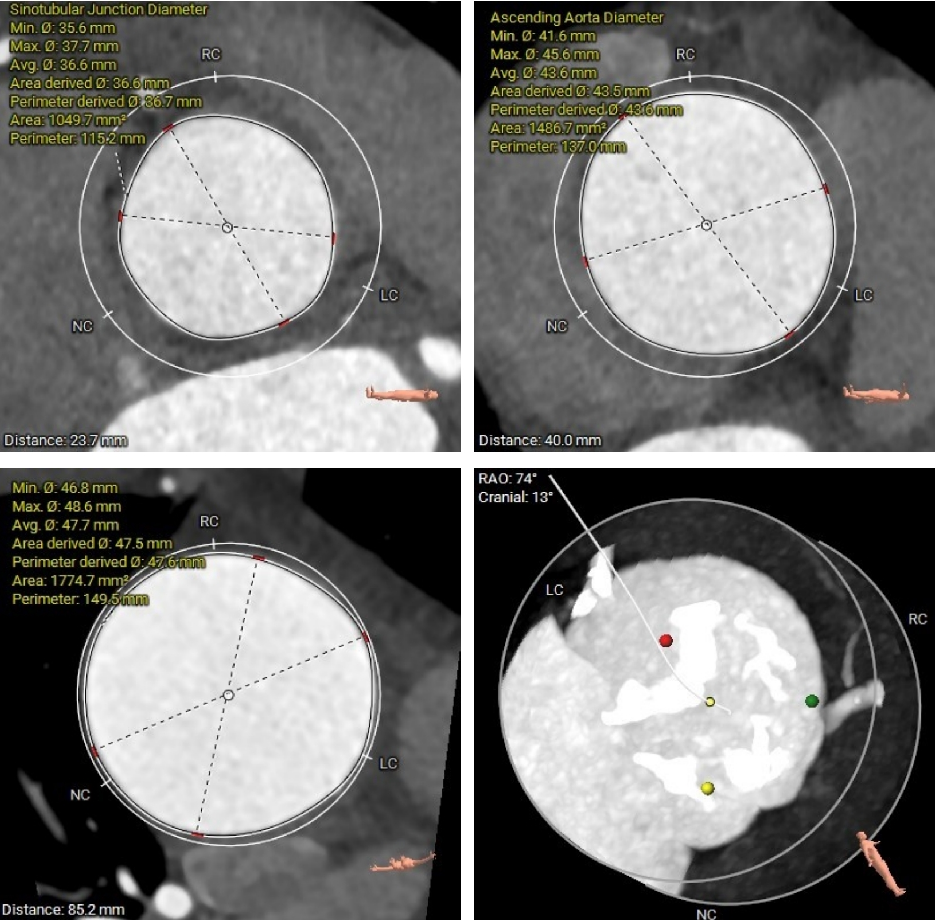

三叶三窦式主动脉瓣

瓣环周长94.5mm,平均周长径30.1mm;

SOV瓦式窦:32.6mm *35.4mm*36.9mm ;

LVOT周长91.9mm,平均周长径 29.2mm。

STJ平面周长115.2mm;

升主动脉最大直径47.6mm;

瓣叶重度钙化合并增厚,钙化分布不均,主要集中于左冠窦内。

HU953 积分862mm²。

左冠高度14.7mm 右冠高度15.1mm;

瓣口对应瓣叶稍冗长,术中须注意冠脉风险。

心脏水平夹角67°,横位心;

左室腔内径尚可,心室壁增厚明显。